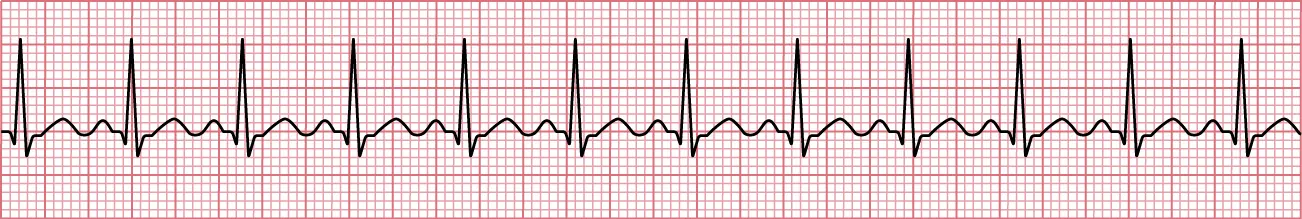

An atrial flutter (A flutter) is an atrial dysrhythmia related to AFib (Figure 12.15). It is a regular but tachycardic rhythm caused by electrical re-entry in the right atrial circuity. The classic “saw tooth pattern” is one of the hallmark features. The PR interval is indeterminate, the QRS interval is less < 0.12, and it is regular. A flutter rates may be 240 to 300 bpm.

Sinus rhythm showing sawtooth pattern classic of atrial flutter.

Figure 12.15 This saw-tooth pattern is classic of A flutter. This rhythm shows a 4:1 ratio, meaning that there are four flutter waves per every QRS complex. There are no discernible P waves. (attribution: Copyright Rice University, OpenStax, under CC BY 4.0 license)